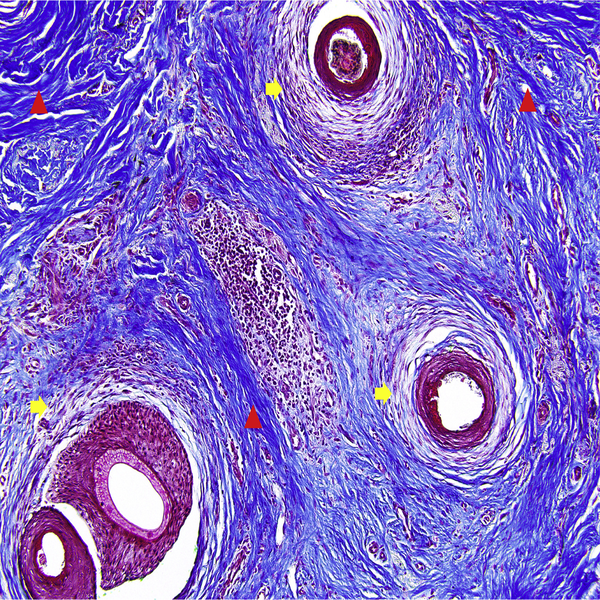

- General and specialized tissue and cell staining

- Preparation of sections from chemical and natural tissue scaffolds

Histological methods includes sample processing in the pathology laboratory, preparation of the slide and its examination under a microscope, sample fixation, molding, microtome cutting, staining and assembly of the slides.